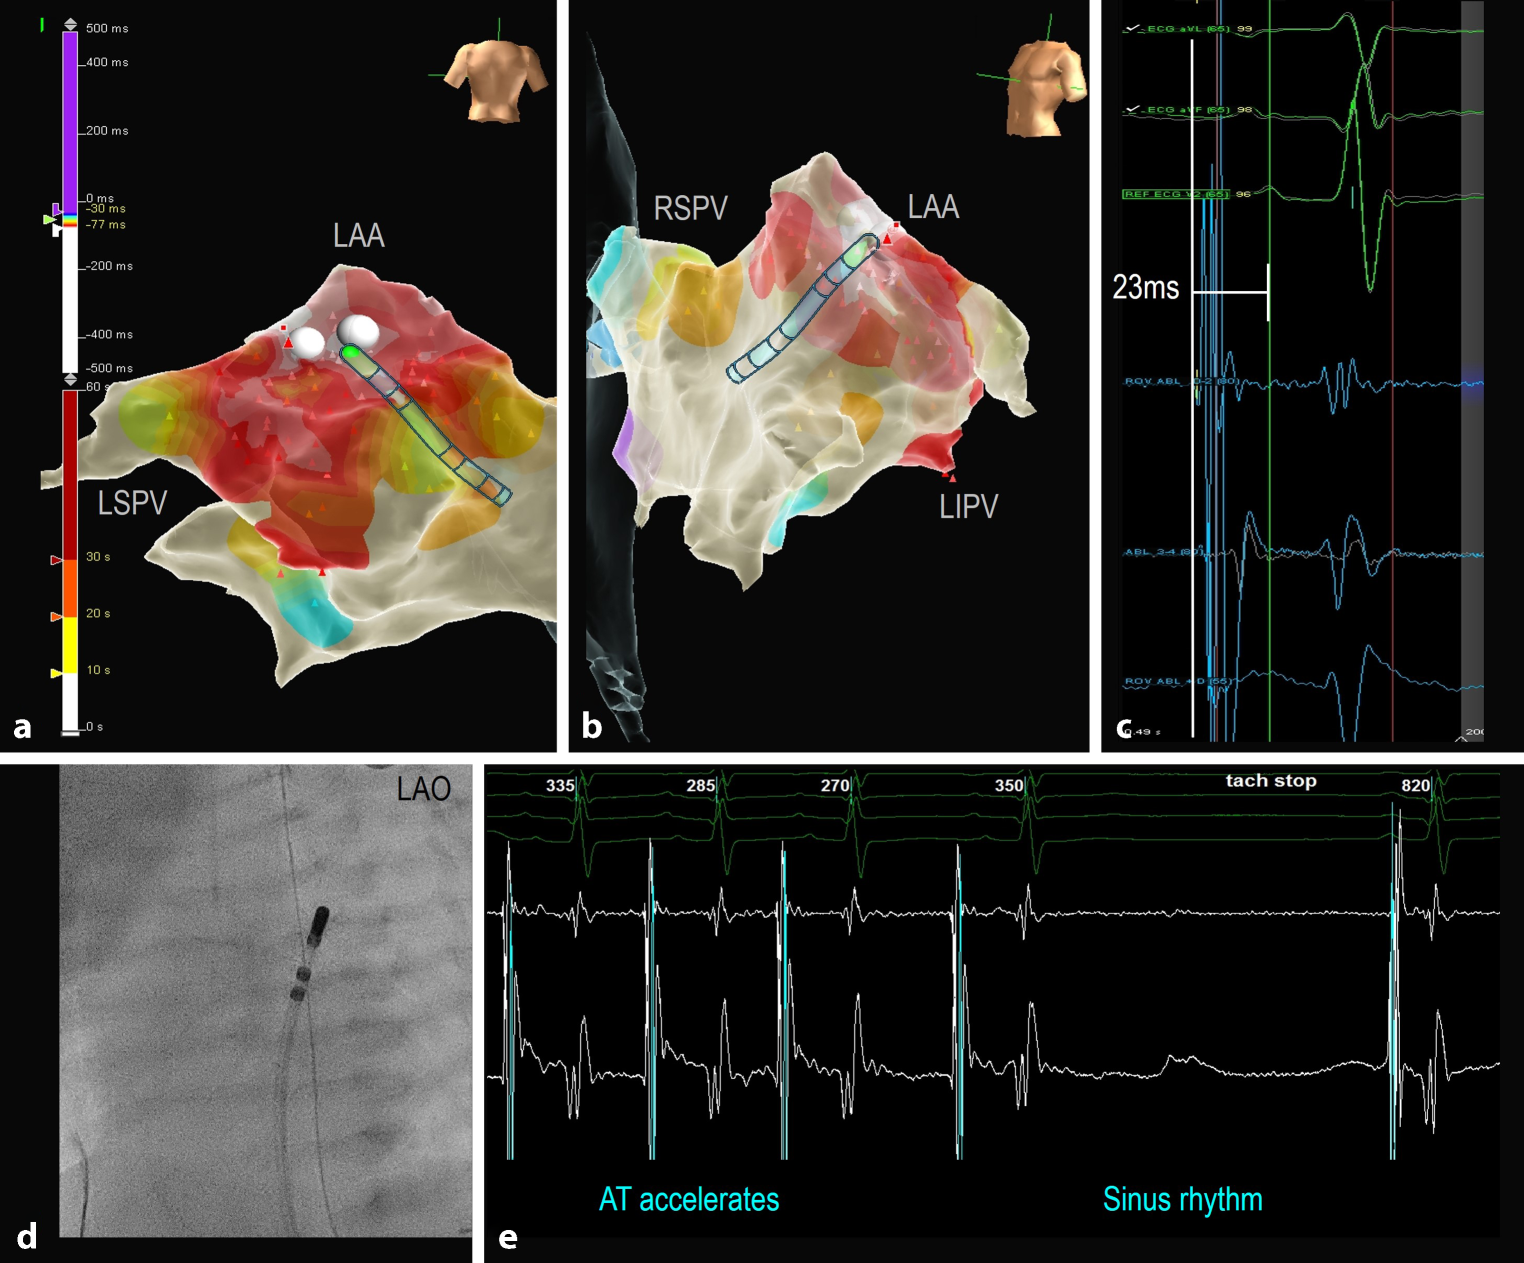

Patient 5 presented with a left-sided incessant focal AT (CL 280–350 ms) and underwent mapping through the PFO using the P wave on the surface ECG as reference. The atrial focus was located in the small left atrial appendage and was successfully ablated with a 7 Fr irrigated tip catheter due to low power from impedance rise with both the non-irrigated 5 and 7 Fr catheters (see Fig. 2).

Fig. 2

Focal atrial tachycardia (AT). Local activation map in PA (a) and LAO (b) views showing the location of the AT focus within the left atrial appendage (LAA). LAO fluoroscopic image (d) demonstrating the single 7 Fr intracardiac mapping/ablation catheter, which was advanced across the PFO to the left atrium and LAA. The onset of the earliest atrial activation recorded in the mapping/ablation catheter (c) precedes the peak of the reference P wave on the surface ECG by 23 ms. RF applications done in this location (a,b) resulted in acceleration and termination of the AT in less than 3 s (e). RF radiofrequency, LAO left anterior oblique, LIPV/LSVP left inferior/superior pulmonary vein, PA posteroanterior, PFO persistent foramen ovale, RSPV right superior pulmonary vein